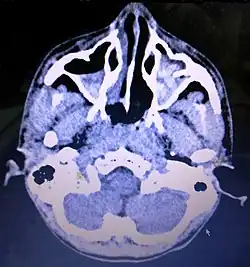

-

Maxillary sinus cancer that has spread to the brain -